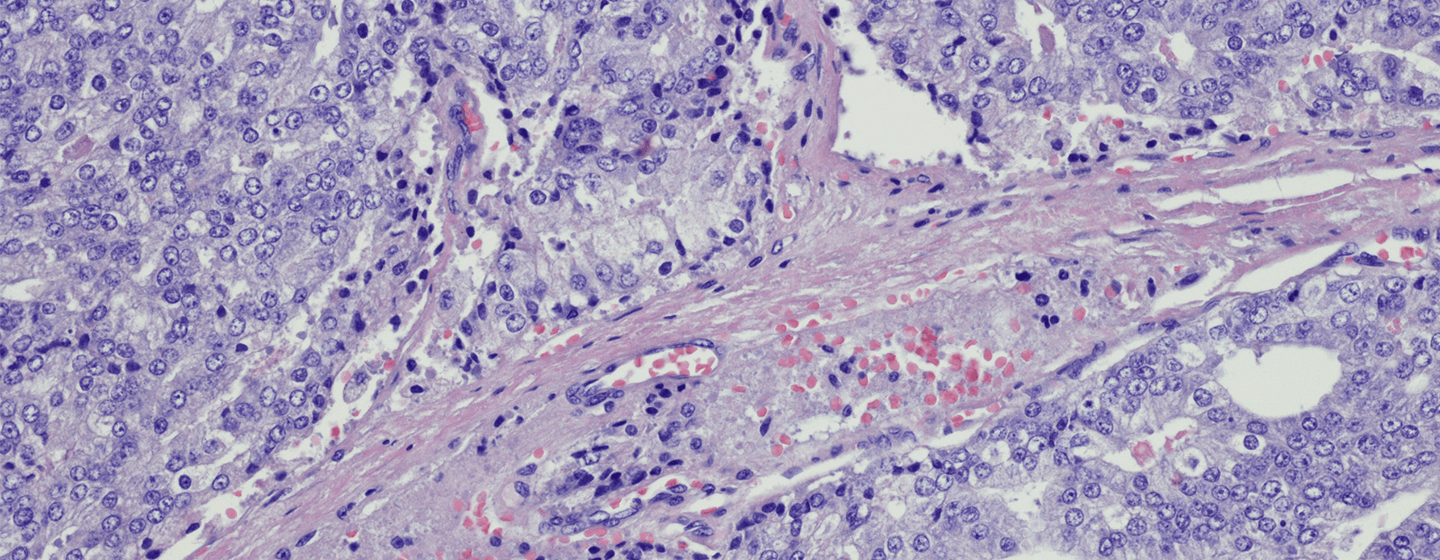

Garvan researchers have revealed changes to the 3D arrangement of DNA linked to treatment resistance in ER+ breast cancer. Epigenetic changes occur in the DNA of breast cancer cells that have developed a resistance to hormone therapy, an effective treatment for ER+ breast cancer, which accounts for 70% of all diagnoses.

A team led by Professor Susan Clark at the Garvan Institute of Medical Research showed that the 3D structure of DNA is ‘rewired’ in hormone resistant ER+ breast cancers, altering which genes are activated and which genes are silenced in the cells. The researchers published the findings today in the journal Nature Communications.

Using chromosome conformation capture, a cutting-edge technique that provides a snapshot of how DNA is arranged and interacts in three dimensions in the cell, the researchers compared different ER+ breast cancer cells that were either sensitive or resistant to hormone treatment.